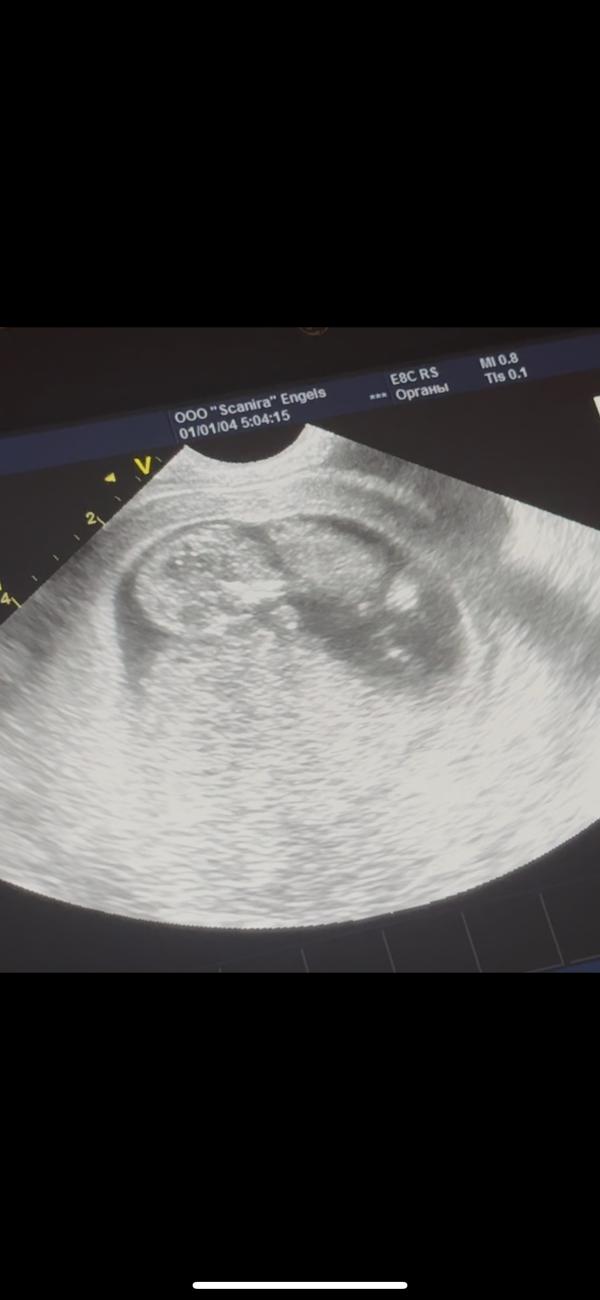

Нормально ли , что малыш так лежит ?

Просто обычно у всех лежит вверх лицом …

У меня на 1 скрининге так же лежал, я удивилась. А врач узи говорит что лежит так как ему удобно)) мы же лежим на животе, на боку, на спине меняем положение тела, вот и он такой же человечек как и мы) но потом она его будила датчиком, и он перевернулся в итоге

Это датчик так поставили

Они они же сами переворачивают картинку